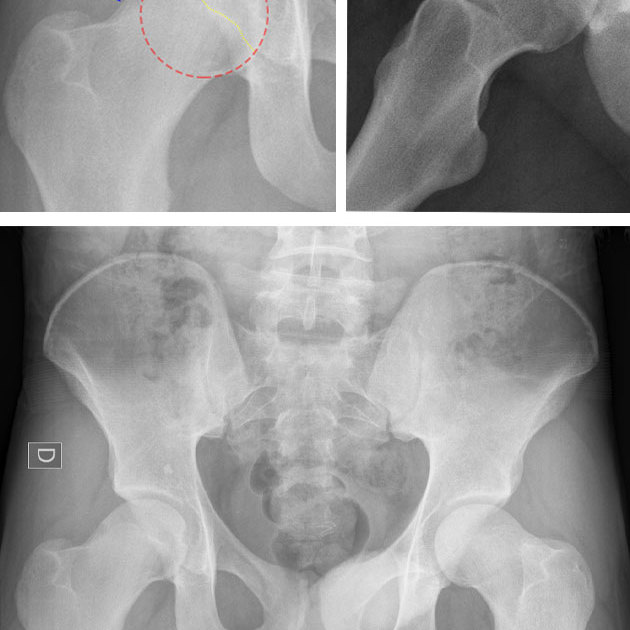

At The Centre for Physical medicine we can help with almost all injuries and conditions of the spine. We also treat shoulder, hip, knee and foot problems; particularly when they are involved in causing problems or pain elsewhere in the body.

We have rapid access to all types of imaging if necessary. We also run a weekly multi disciplinary team meeting. It is an enviable academic environment and is attended by orthopaedic and neuro-surgeons as well as sports physicians and rheumatologists, osteopaths and other physical therapy colleagues who are specialists in their fields. We present difficult cases or second opinion cases. It is available to our patients.